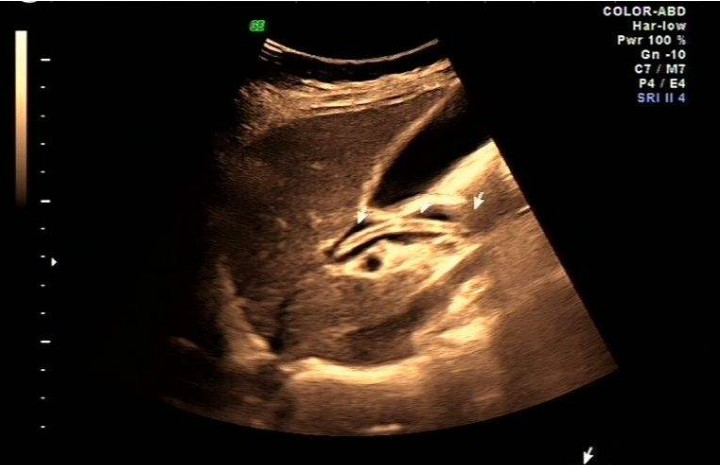

胆道蛔虫症是人体感染了蛔虫病之后最常见的并发症。,蛔虫平时常寄生在人的小肠里,一旦环境有变化,比如感冒发烧、饥饿、腹泻、驱虫治疗不正确的或药量不足以及蛔虫身受到刺激,都可以上窜到十二指肠和胃内,蛔虫本身也有钻孔习性并喜欢碱性胆汁,所以很容易钻入胆道在十二指肠的开口,进入胆总管,甚至进入左右肝管,也可以窜入胆囊,这就是胆道蛔虫症,实际上蛔虫,很少窜入胆囊,最多见的是窜入胆总管。

胆道蛔虫症俗称“蛔虫入苦胆”(指胆囊)实际上蛔虫很少进入胆囊内,而是进入了排泄胆汁的管道中,这样就严重刺激了胆道,首先引起胆道开口处(即在十二指肠)肌肉(医学上称之为奥迪氏括约肌)的强烈痉挛和胆道强烈的收缩,而引起上腹部心口窝处(剑突下)剧烈的疼痛,进入胆道的虫体数目大多为1-5条,最多可数十条甚至百余条,虫体自行从胆道退出疼痛缓解;一条虫体退出后,又有其它虫体重新钻入,虫体不断的刺激胆道口扩约肌引起阵发性强烈收缩,使得病人会阵发性剧烈腹疼而辗转不安;若虫体完全钻入胆道,甚至进入胆囊,疼痛就反而减轻。